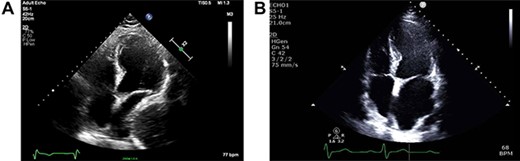

As part of the assessment, computed tomography (CT) coronary angiogram study was performed and it demonstrated a large fluid-filled oesophagus causing partial compression of the left atrium. Barium swallow (Fig. 1A and B), CT chest and abdomen (Fig. 2A and B) and transthoracic echocardiography (TTE) showed a 7.1-cm dilated oesophagus causing left atrial compression and a small hiatal hernia (Fig. 3).

(A) ECHO showing left atrial compression from megaoesophagus during diastole; (B) ECHO showing normal-sized left atrium 3 months after band removal.